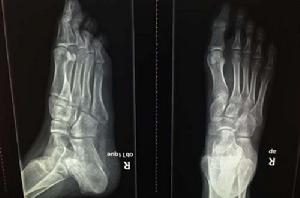

跖骨:跖骨近側為底,中部為體,遠側端為頭。

人體位置在人體中,每足有五塊,連於踇趾的稱第一跖骨,以下依次為第二至第五跖骨。

本病多見於青少年,一般多在13歲以後發病,尤以8-17歲的女孩多見,約占75%。左右測發病相近,10%為雙側同時發病。多見於第二跖骨頭,遇見其他跖骨頭。受累的跖趾關節常過伸,活動明顯受限制,強行屈曲或用足尖著地時,疼痛加重。有事可觸及跖骨頭粗大、壓痛。病人足弓較低,橫弓鬆弛,或伴有輕度跛行。後期因跖骨頭膨大,關節面不平整,有骨贅增生而壓迫其下趾神經,引起持續性疼痛,關節和有摩擦音。